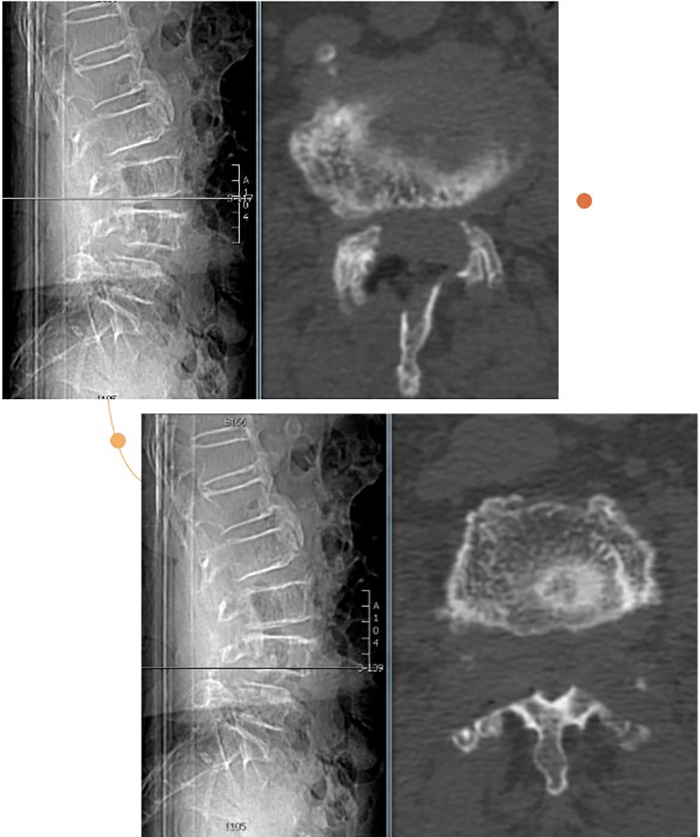

陈瑞松副主任医师接诊后,经过详细询问病史、全面查体,并结合影像学检查,诊断为腰椎椎管重度狭窄症。考虑到张阿婆年事已高,有高血压、冠心病、糖尿病、骨质疏松病史,陈瑞松副主任医师建议其采用微创手术治疗。据介绍,相较于常规开放手术,脊柱微创手术有创伤小、出血少、恢复快等优点,是高龄患者的福音。

术前影像

经过详细的术前评估和完善的术前准备,陈瑞松带领团队为张阿婆进行一个节段的单侧入路双侧减压(ULBD)手术及一个节段的双侧入路270度减压手术,仅切开了三个7毫米的小切口,一个多小时就顺利完成手术。